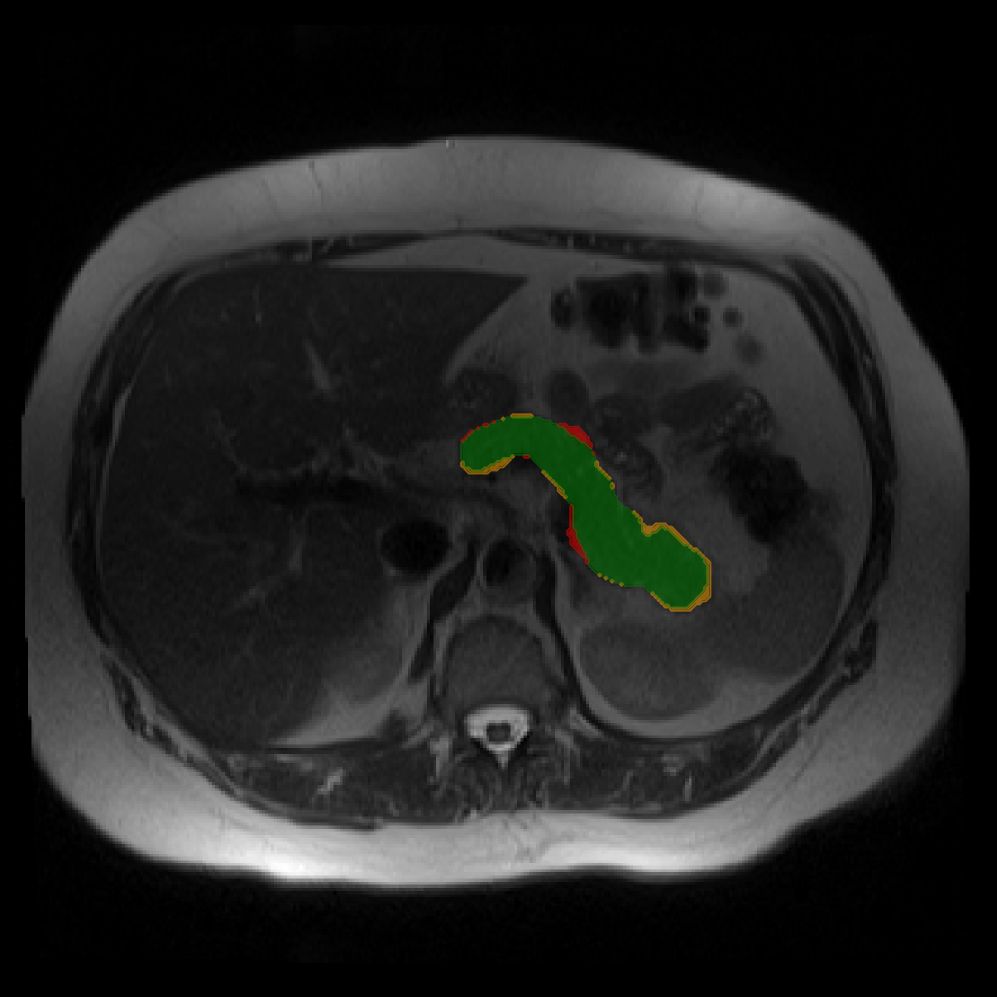

Accurate pancreas segmentation is a critical prerequisite for precise cyst analysis and classification. Recently, we developed PanSegNet [zhang2025large], a novel segmentation architecture incorporating linear self-attention layers [zhang2022dynamic] within the nnUNet framework [isensee2021nnu] to enhance global information modeling capabilities while maintaining computational efficiency (Fig. 1). PanSegNet demonstrated exceptional segmentation performance across both T1W and T2W modalities, achieving mean dice scores of 86.817.30% and 89.626.38%, respectively (Table 1, Fig. 2b-c). This performance significantly exceeded that of Swin-UNETR [hatamizadeh2021swin], one of the most used state-of-the-art transformer-based medical segmentation models, which achieved dice scores of 79.091.40% and 76.290.66% for T1W and T2W, respectively (). In this study, we integrated PanSegNet into our Cyst-X engine along with a classifier for risk prediction. In Section 2.2, we show that the choice of segmentation model affects the classification results. The performance advantage of PanSegNet was consistent across all seven medical centers, demonstrating robust generalization despite variations in imaging protocols and equipment (Table 1). This cross-institutional reliability is particularly important for clinical applications, where model performance must remain consistent regardless of imaging site or acquisition parameters.

2.2.1 Importance of accurate pancreas segmentation in classification

To assess the importance of accurate pancreas segmentation in classification, we evaluated how different ROI sources affect DenseNet-121’s performance. Specifically, we compared classification results using ROIs generated by PanSegNet and Swin-UNETR, both under centralized learning, against a baseline using radiologist-defined ROIs. As shown in Table 2, using PanSegNet’s masks resulted in only a modest performance decline, reflecting its strong segmentation quality. In contrast, Swin-UNETR led to a more substantial drop, demonstrating that inferior segmentation can directly compromise classification. For 3-class classification, the mean AUC dropped from 75.59% (radiologist ROI) to 72.26% with PanSegNet, and further to 66.95% with Swin-UNETR on T1-weighted images. On T2-weighted scans, the AUC declined from 81.09% to 74.18% (PanSegNet) and to 69.63% (Swin-UNETR). A similar trend was observed in 2-class classification: on T1W, AUC dropped from 78.13% to 74.84% (PanSegNet) and 70.20% (Swin-UNETR); on T2W, from 82.37% to 77.01% and 68.92%, respectively. These results emphasize that accurate segmentation—particularly via PanSegNet—is not only essential for volume estimation but also critical to preserving downstream classification performance in the Cyst-X pipeline.

Each patient was categorized into one of these three ground truth classes: no risk/control, IPMN low-risk, or IPMN high-risk. To evaluate variability in image acquisition, we applied uniform manifold approximation and projection (UMAP) to image quality indicators, revealing distinct clustering patterns by imaging center and slice thickness. This heterogeneity reflects real-world clinical variability, enhancing the dataset’s generalizability while presenting technical challenges for model development. Fig. 6 shows examples of low-grade, high-grade, and cancer developing IPMNs from the Cyst-X dataset.